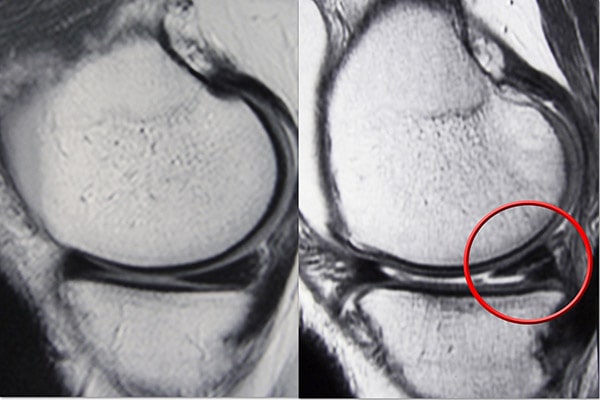

成像測試

由于其他膝蓋受傷也會引起類似的癥狀,您的醫生可能會要求進行影像學檢查以幫助確認診斷。

磁共振成像 (MRI) 掃描。 MRI 掃描可評估膝關節的軟組織,包括半月板、軟骨、肌腱和韌帶。